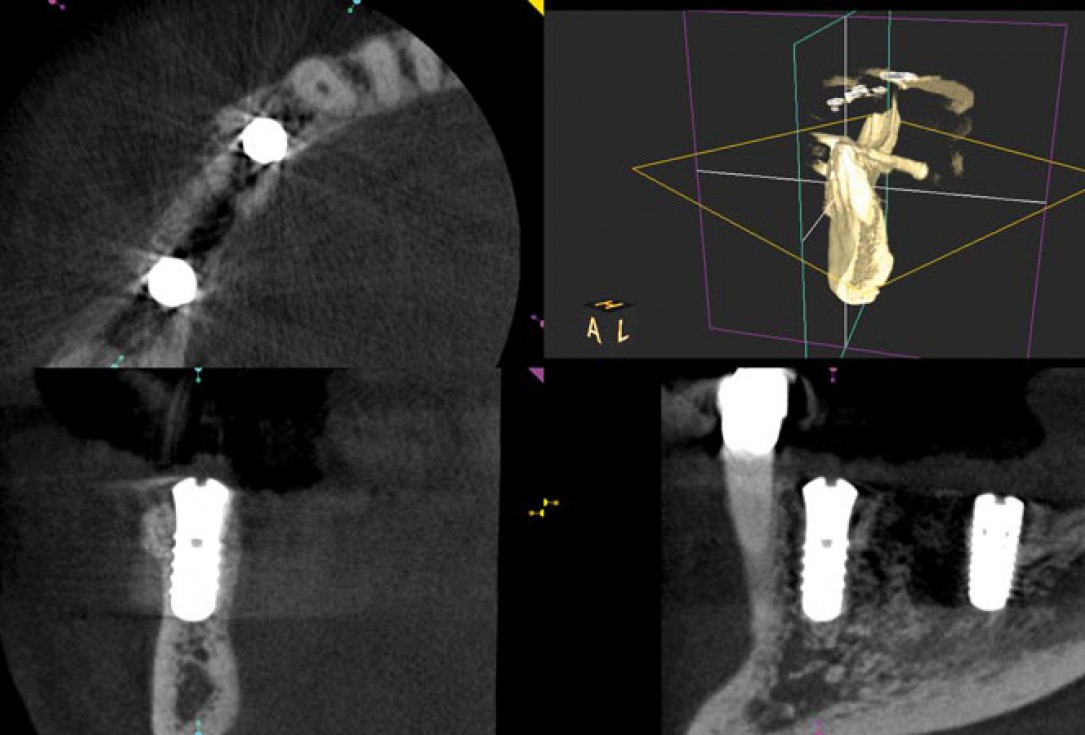

11/14 - CBCT scan post implantation

Block augmentation with maxgraft® in the mandible - PD Dr. Dr. F. Kloss